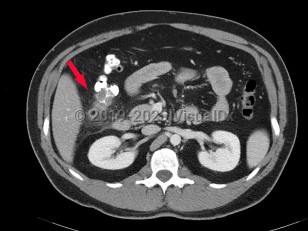

Diverticulitis is a disease characterized by inflammation in colonic diverticula. Cases are classified as uncomplicated or complicated on the basis of clinical and radiographic features. Uncomplicated cases are characterized by clinically stable patients with inflammation in a localized area of the bowel wall. By contrast, complicated disease is defined by the presence of abscess, phlegmon, fistula formation, obstruction (large bowel, small bowel), bleeding, perforation, or peritonitis, which are collectively present in about 12% of cases.

Patients classically present with abdominal pain (typically left lower quadrant), nausea and/or emesis, and fevers. Changes in bowel habits including loose, sometimes bloody bowel movements, as well as constipation, can occur. The prevalence is strongly associated with age and is most common in adults aged older than 50 years, although the incidence in younger populations has increased steadily in recent decades.